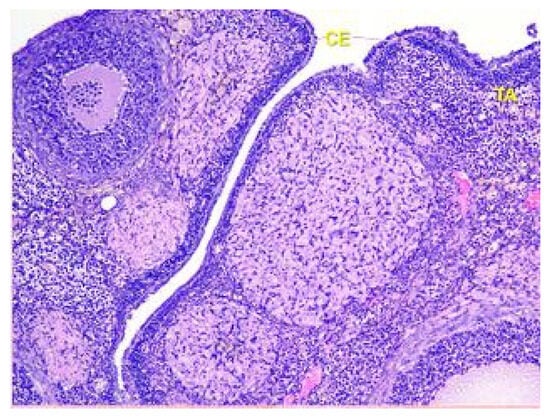

- Denefil, O.V.; Bilyk, Y.O.; Chorniy, S.V.; Fedoniuk, L.Y.; Chornii, N.V. The peculiarities of morpological changes of rats’ ovary and biochemical state under the damage with different doses of lead acetate. Wiad Lek. 2022, 75, 377–382. [Google Scholar] [CrossRef] [PubMed]